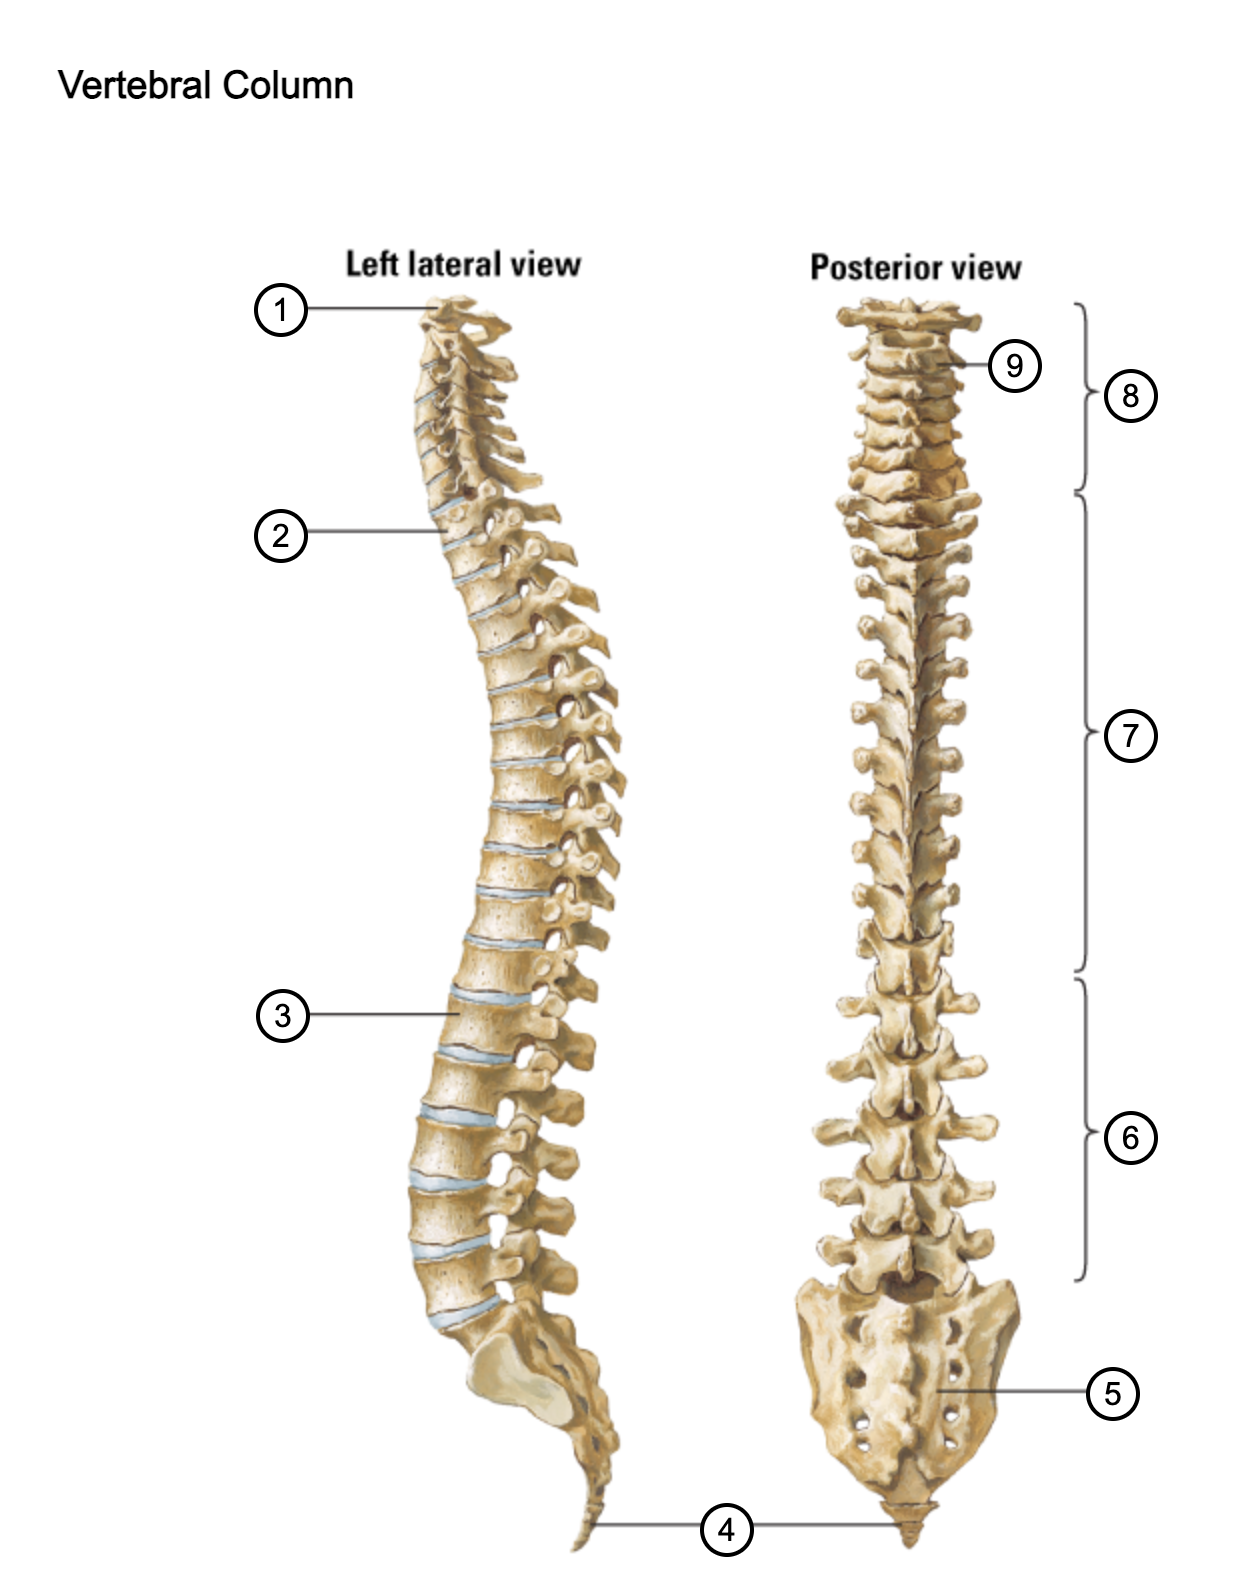

1

atlas (C1)

2

T1

3

L1

4

coccyx

5

sacrum (S1-5)

6

lumbar vertebrae

7

thoracic vertebrae

8

cervical vertebrae

9

axis (C2)